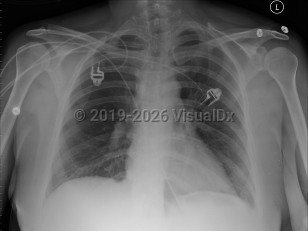

Congestive heart failureCongestive heart failure

Cardiogenic shock